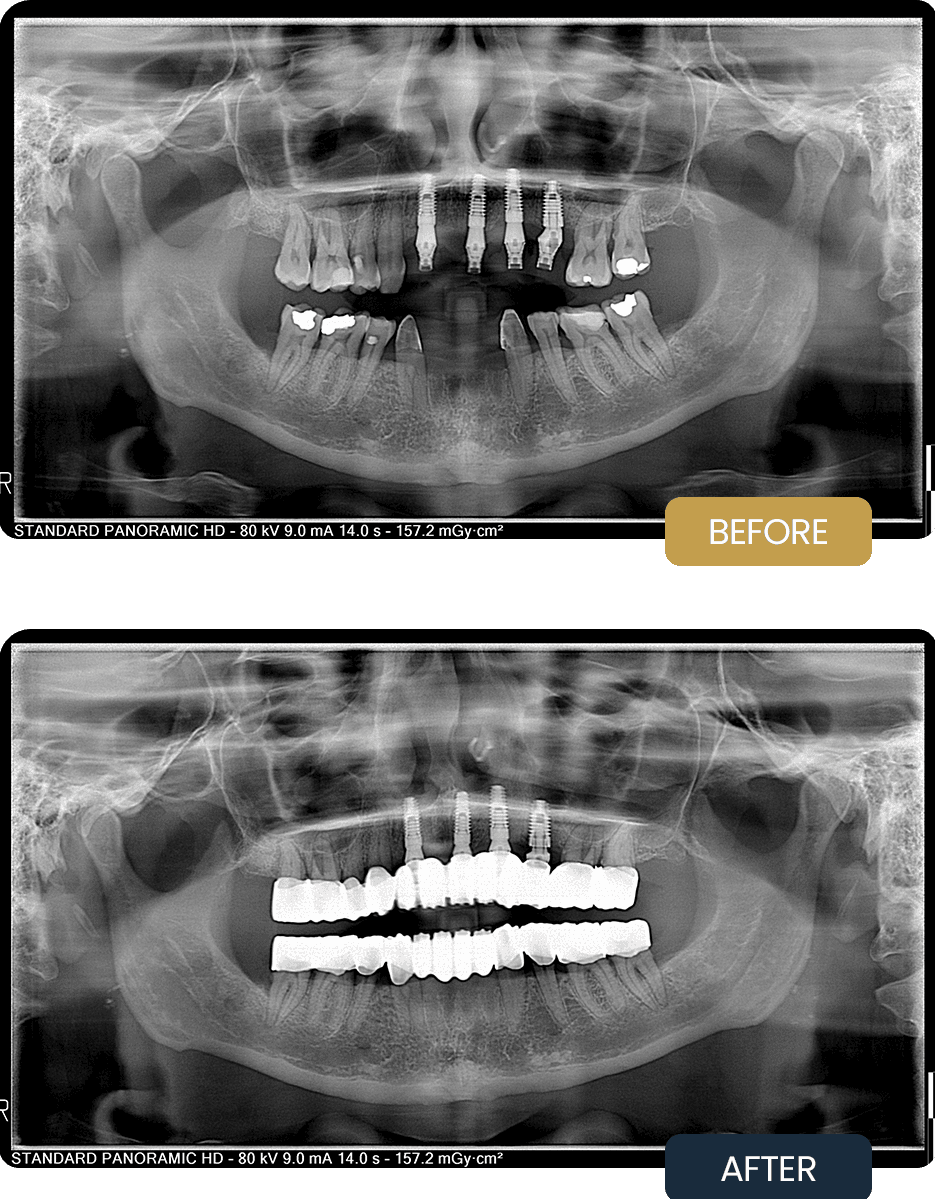

At initial presentation, Claire exhibited multiple compromised teeth, existing restorations, and missing teeth that affected smile aesthetics and functional balance. The pre treatment panoramic radiograph illustrates the condition of the remaining dentition and the need for both implant placement and full coverage restorations.

Post treatment panoramic imaging confirmed stable, well integrated implants supporting the final restorations. The zirconium crowns provided a uniform, natural looking smile with improved function, proper occlusion, and enhanced long term comfort.